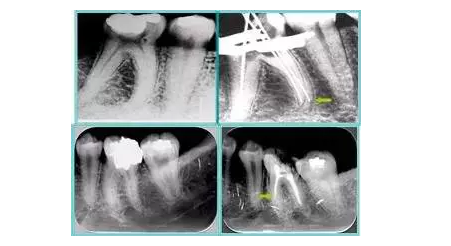

6. 術(shù)后 X 線片

術(shù)后 X 線片用來評定根管充填 長度、致密度(管壁清晰、側(cè)枝)等指標(biāo)。

左圖為根管充填術(shù)后 X 線片。圖中可見,根管充填較好。右下圖有白色小點(diǎn),為側(cè)方加壓導(dǎo)致糊劑擠出所致,表明根管充填比較致密。

致密、恰到好處的充填可去除干凈根管里感染灶,機(jī)體逐漸恢復(fù)。

多根牙時候需進(jìn)行偏移投照,正位投照無法說明具體哪根牙根管充填效果。 二、根管預(yù)備及充填要求